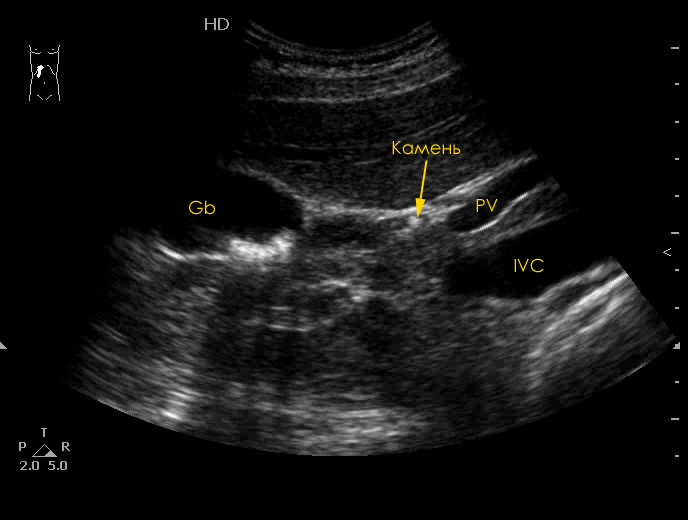

УЗИ ЖВП: конкремент в пузырном протоке

Воротная вена как раз и видна, точнее ее левая ветвь.

1.jpg